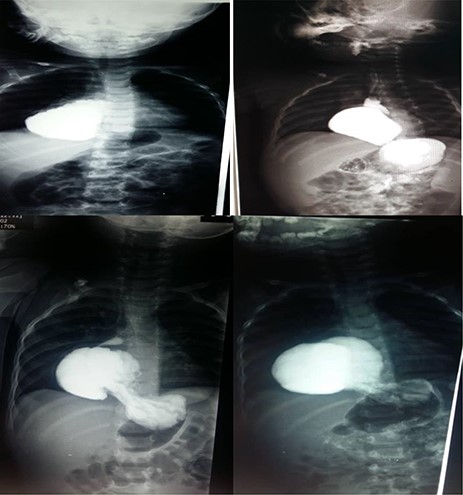

A 38-month-old girl was admitted with 2-week history of epigastric pain and 10-day history of appetite loss. Labs showed normal CBC with a slight anaemia (Hb: 11.9 g/dl). Endoscopy showed a displacement of the LES with a stricture in the lower third. The barium meal showed the abdominal viscera protruding into the chest with left mediastinal displacement (see Fig. 3). Open surgery showed stomach protrusion into the thoracic cavity which was fixed in the abdominal cavity with diaphragm repair.

Upper left photo is of case two that shows a barium swallow with 5.5 cm hiatus hernia. The upper right photo is of case 4 that shows a barium swallow with 8 cm hiatus hernia. Lower 2 photos are of case 3 that show barium swallow with a 6 cm hiatus hernia.

An 18-month-old boy was admitted to the Children Hospital with a 3-week history of progressive pallor and 1 day history of melena after which his parents brought him to a private clinic when a chest X-ray showed that he had HH with the stomach being in the chest cavity with an enlarged left pulmonary hilum and right mediastinum displacements (see Fig. 3). CBC showed that he was also severely anaemic (Hb: 6 g/dl). He reported no other symptoms and had not been prescribed any previous medications. An endoscopy was performed which showed an abnormal location of the stomach in the thoracic cavity. The barium meal was obtained which confirmed the HH. In open surgery from the abdomen, the stomach and the oesophageal hiatus were found to be herniated into the thoracic cavity. They were repaired with Nissen surgery.

An 8-month-old boy was admitted with a 20-day history of black, loose diarrhoea (5–6 occurrences in total) with no frank blood in the stool. He had low fever. Lab tests were normal with positive stool occult blood test. Following symptomatic treatment for 2 weeks, an endoscopy was conducted which showed a displacement of the LES with mild lower ulcerative oesophagitis and was confirmed later on with a plain X-ray and a barium meal to be an 8 cm HH (see Fig. 3). The HH was repaired with Nissen open surgery.